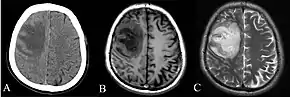

CT and MRI scans showing lesion of the right frontal lobe of the brain.[6]

Depending on the course of infection, other severe manifestations develop. Approximately 1 to 5% of those infected develop inflammation of the brain and brain covering or brain abscess; 14 to 28% develop pyelonephritis, kidney abscess or prostatic abscesses; 0 to 30% develop neck or salivary gland abscesses; 10 to 33% develop liver, spleen, or paraintestinal abscesses; and 4 to 14% develop septic arthritis and osteomyelitis.[1] Rare manifestations include lymph node disease resembling tuberculosis,[10] mediastinal masses, pericardial effusion,[3] mycotic aneurysm,[1] and inflammation of the pancreas.[3] In Australia, up to 20% of infected males develop prostatic abscess which may manifests clinically as pain during urination, difficulty in passing urine, and urinary retention requiring catheterisation.[1] Rectal examination may find enlarged prostate.[3] In Thailand, 30% of the infected children develop parotid abscesses.[1] Encephalomyelitis not only happens in those with risk factors, but can also occur in healthy people without risk factors. Those with melioidosis encephomyelitis tend to have normal computed tomography (CT) scans but increased T2 signal by magnetic resonance imaging (MRI), extending to the brain stem and spinal cord. Clinical signs include: unilateral upper motor neuron limb weakness, cerebellar signs, and cranial nerve palsies (VI, VII nerve palsies and bulbar palsy). Some cases presented with flaccid paralysis alone.[3] In northern Australia, all melioidosis with encephalomyelitis cases had elevated white cells in the cerebrospinal fluid (CSF), mostly mononuclear cells with elevated CSF protein.[10]

Various imaging modalities can also help with the diagnosis of melioidosis. In acute melioidosis with the spreading of the bacteria through the bloodstream, the chest X-ray shows multifocal nodular lesions. It may also show merging nodules or cavitations. For those with acute melioidosis without the spread to the bloodstream, chest x-ray most commonly shows upper lobe consolidation or cavitations.[10] In chronic melioidosis, the slowly progressing of upper lobe consolidation of the lungs resembles tuberculosis.[10] For abscesses located in other parts of the body apart from the lungs, especially in the liver and spleen, CT scan has higher sensitivity when compared with an ultrasound scan. In liver and splenic abscesses, an ultrasound scan shows "target-like" lesions while CT scan shows "honeycomb sign" (abscess with loculations separated by thin septa) in liver abscesses.[10] For melioidosis involving the brain, MRI have higher sensitivity than a CT scan in diagnosing the lesion. MRI shows ring-enhancing lesions for brain melioidosis.[10]